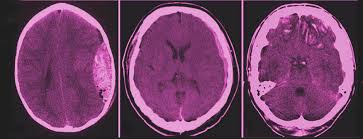

Was ist ein schädel hirn trauma. 2 Ätiologie Schädel-Hirn-Traumen entstehen durch Gewalteinwirkungen auf den Schädel und sind eine häufige Verletzung bei Stürzen und Unfällen. Das Schädel-Hirn-Trauma bezeichnet eine offene oder gedeckte Verletzung des Schädels und des Gehirns durch äußere Gewalteinflüsse. Wie gefährlich ist dieses und was ist es genau.

Ein Schädel-Hirn-Trauma kurz SHT ist eine Verletzung Trauma des Schädelknochens die mit einer Schädigung des Gehirns einhergeht. Egal ob ein unglückliches Ereignis beim Sport oder ein Autounfall schuld an einem Schädel-Hirn-Trauma kurz SHT ist die Verletzung trifft jeden unerwartet und verändert in schweren Fällen mit einem Schlag das komplette Leben. Das Schädel-Hirn-Trauma bezeichnet unterschiedlichste Kopfverletzungen die ihrerseits zu Verletzungen und Funktionsstörungen des Gehirns führen.

Unter einem Schädel-Hirn-Trauma versteht man Verletzungen des Schädels mit Beteiligung des Gehirns. Es führt zu Funktionseinschränkungen die sich je nach Schweregrad wieder zurückbilden können oder dauerhaft bestehen. Dies kann ein Aufprall ein Stoß oder ein Schlag sein weswegen das Hirn gegen den Schädelknochen schlägt.